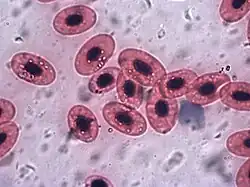

In non-mammals

Human blood is typical of that of mammals, although the precise details concerning cell numbers, size, protein structure, and so on, vary somewhat between species. In non-mammalian vertebrates, however, there are some key differences:[19]

- Red blood cells of non-mammalian vertebrates are flattened and ovoid in form, and retain their cell nuclei.

- There is considerable variation in the types and proportions of white blood cells; for example, acidophils are generally more common than in humans.

- Platelets are unique to mammals; in other vertebrates, small nucleated, spindle cells called thrombocytes are responsible for blood clotting instead.